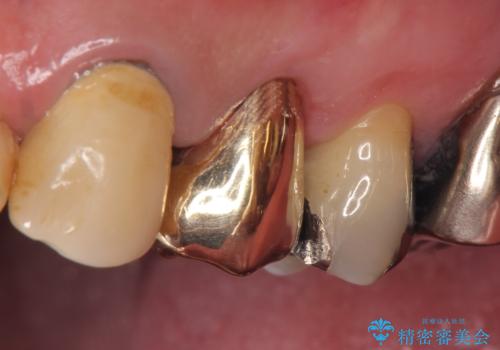

PGA(ゴールド)クラウン 脱離した銀歯の治療

再根管治療後、PGA(ゴールド)クラウンによる補綴を行いました。

PGA(ゴールド)治療について

ゴールドは化学的な安定性が高いため変色や腐食がほとんどなく、アレルギーなども起こりにくい人体に優しい素材です。

また硬さも天然歯に近いため周囲の歯への影響も少なく、さらに適合もよいため虫歯の再発も少ない、とても補綴に適した材料です。